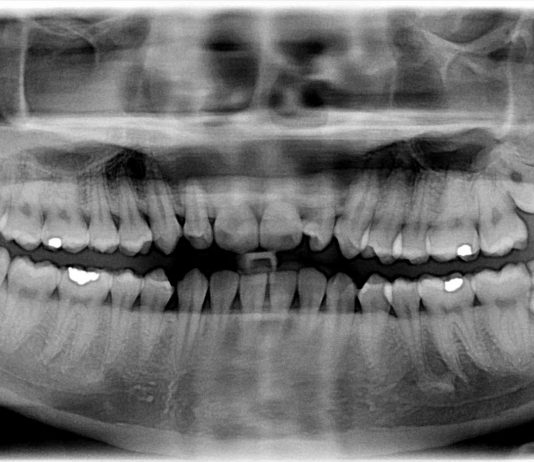

Wisdom teeth are the most posterior of all molars, residing in the far back corners of your mouth. They can emerge at any time, typically between 17 and 25, and often affect surrounding teeth as they come in. During a trip to the dentist, an X-ray can show how...